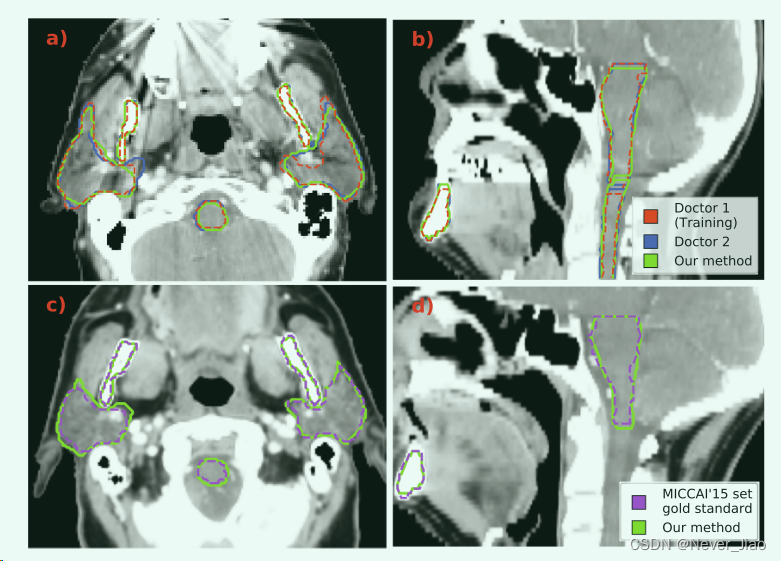

In the figure 4 in , We illustrate the example segmentation generated by our proposed method . chart 4a and 4b Shows patients from our original data set 2D Axial and sagittal slices . chart 4c and 4d It is used for external verification MICCAI’15 Examples of centralized patients .

Fig.4 our CNN Example segmentation of model generation ( green ). In the first line a) and b) in , We show patients from the dataset we used for model development 2D Axial and sagittal views . The dataset contains segmentation generated by two doctors , Displayed in red and blue . At the bottom c) and d) in , We've shown people from MICCAI’15 Axial and sagittal of patients in group 2D section . The golden standard section of the collection is displayed in purple .